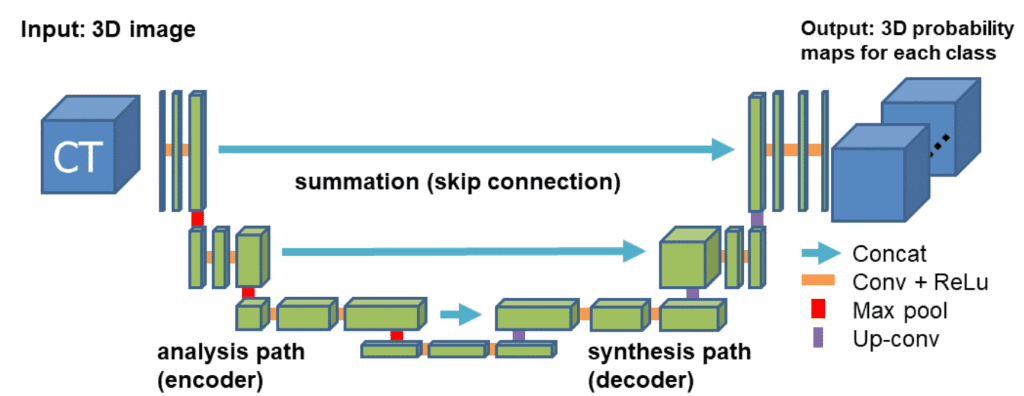

对于我们的示例,我们将使用广为接受的 3D U 形网络。后者(代码)扩展了对称 u 形 2D Unet 网络的连续概念,该网络在 RGB 相关任务(例如语义分割)中产生了令人印象深刻的结果。该模型有一个编码器(收缩路径)和一个解码器(合成路径)路径,每个路径都有四个分辨率步骤。在编码器路径中,每一层包含两个 3 ×3 ×3 卷积,每个卷积后面跟着一个整流线性单元 (ReLu),然后是一个 2 ×2 ×2 最大池化,每个维度的步幅为 2。在解码器路径中,每一层由一个 2×2×2 的转置卷积组成,每个维度的步幅为 2,然后是两个 3×3×3 的卷积,每个卷积后面是一个 ReLu。快捷方式跳过连接来自分析路径中相同分辨率的层为合成路径提供了必要的高分辨率特征。在最后一层,一个 1×1×1 的卷积将输出通道的数量减少到标签的数量。通过在最大池化之前将通道数加倍来避免瓶颈。在每个 ReLU 之前引入了3D批量归一化。每个批次在训练期间使用其平均值和标准差进行归一化,并使用这些值更新全局统计数据。接下来是一个明确学习规模和偏差的层。下图说明了网络架构。